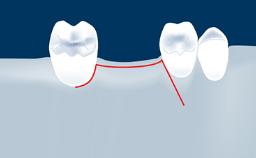

Digitally Guided Sinus Floor Elevation

In this short microlearning module on digitally guided sinus floor elevation, we delve into a specialized aspect of the digital workflow for implant-guided surgery, focusing on the use of digital guides in the sinus floor elevation technique.

- describe the indications for digital guides in SFE